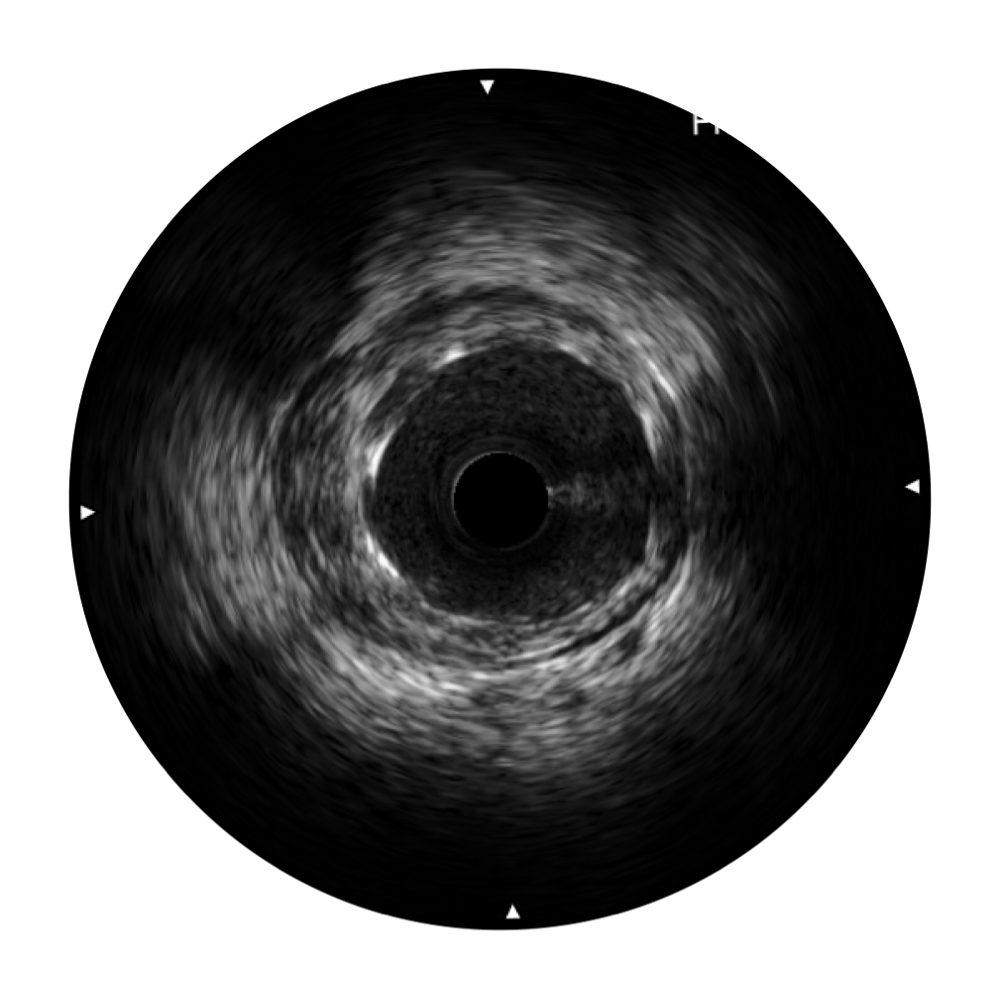

传统IVUS图像

对比传统IVUS导管成像,竞技宝(JJB)官方网站宽频IVUS图像的近场支架梁显影更细腻,远场中膜外血管仍清晰可辨,兼顾远中近,兼顾分辨力与穿透深度